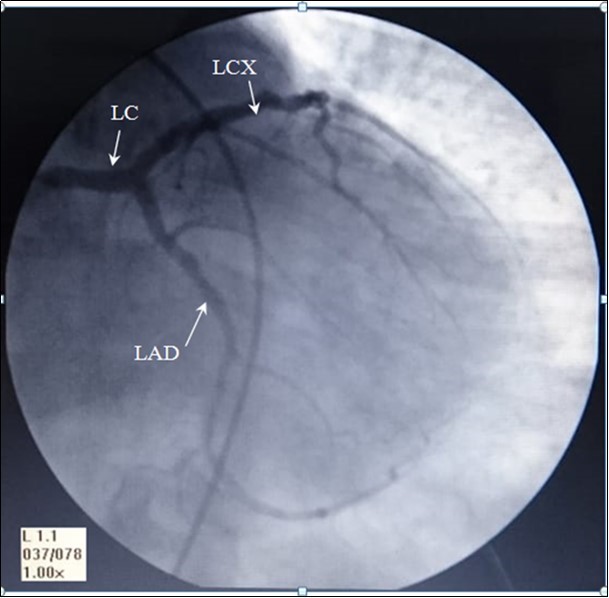

The angiography of these arteries is illustrated in Figure 1.

Figure 1.AP- anteroposterior angiographic view showing, Left coronary artery: LC, left anterior interventricular ( anterior descending) artery: LAD, and Left Circumflex artery: LCX

The angiographic measurement of the left coronary (LC) diameter was found in the range between 2.90- 4.90mm, mean 3.96, and Std. Dev. 0.549mm. The left circumflex artery's diameter was found in the range between1.70- 4.70mm, mean 2.73 and Std. Deviation .687mm. The diameter of the anterior interventricular artery was found in the range between 1.20- 4.70mm, mean 2.78, and Std. Deviation .825mm. these diameters are blotted in the Graph 1.